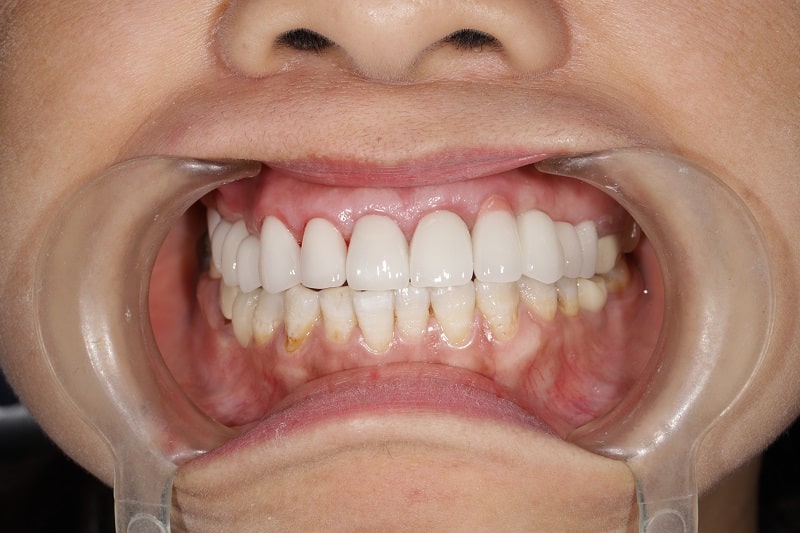

Trám răng thẩm mỹ là gì? Có những loại nào? Lưu ý gì?